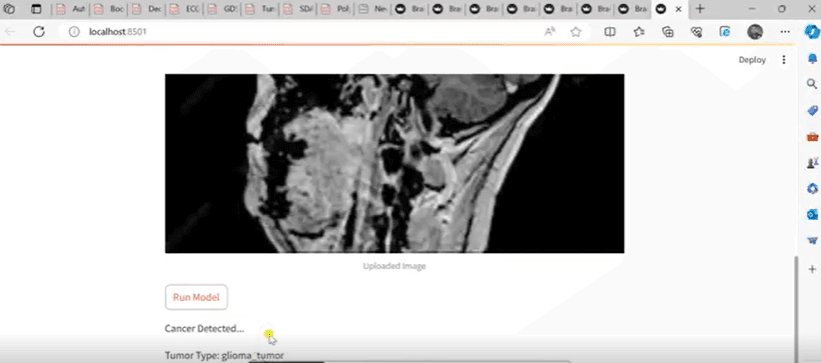

Brain Cancer Detection